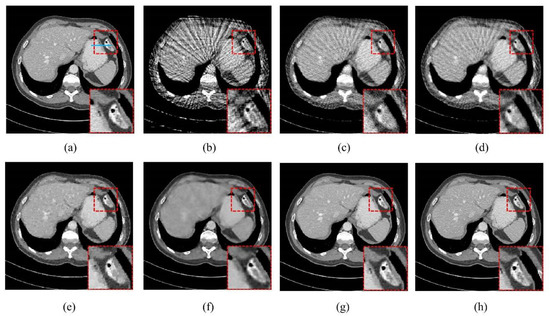

4.1. Visualization-Based Evaluation